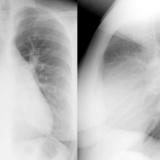

ASD 1 PA&Lat